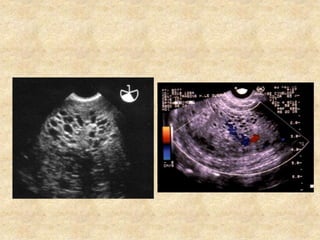

Position du cœur

VD

VG

OD

OG

Aspect des gros vaisseaux

Aspect des grosvaisseaux